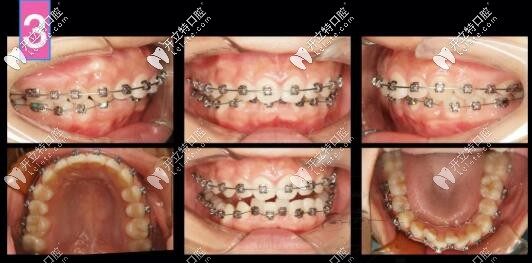

計(jì)劃支抗釘整體推上頜牙列向后、壓低上牙來(lái)解決深覆合和微凸問(wèn)題,選用了標(biāo)準(zhǔn)轉(zhuǎn)矩DamonQ托槽。

凸嘴自鎖托槽矯正案例

第6個(gè)月,上下都排齊了,下頜還是沒(méi)有主動(dòng)跑出來(lái),此時(shí)詞用支抗釘整體上牙內(nèi)收再看看

凸嘴支抗釘內(nèi)收

到了第八個(gè)月,嘴更凸了,因?yàn)樯锨把阑謴?fù)直立于牙槽骨中,凸度增加,臉頰還凹了,

因?yàn)橄虑把来絻A出去,磨牙伸長(zhǎng),深覆合解決,下頜平面角加大

正畸拔牙

此時(shí)再來(lái)看看是否能拔牙

兩項(xiàng)指標(biāo)變了,可以拔牙,

治療計(jì)劃更新:拔上4下5,左側(cè)維持關(guān)系,拔上4下4

齙牙深復(fù)合牙齒矯正案例

前牙區(qū)支抗釘安排上!